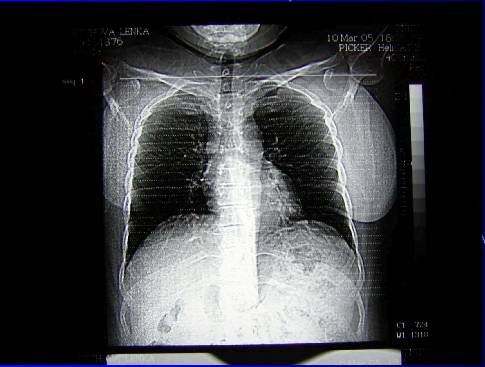

2.Duplicita (pac.H.M.– RTG,CT, CT-PET,UZ,bronchoskopie,cytologie, chirurgická intervence -biopsie -karcinoid)

Duplicita (pac.H.M. . ––RTG,CT,UZ, CT-PET,bronchoskopie,cytologie, chirurgická intervence-biopsie -karcinoid)